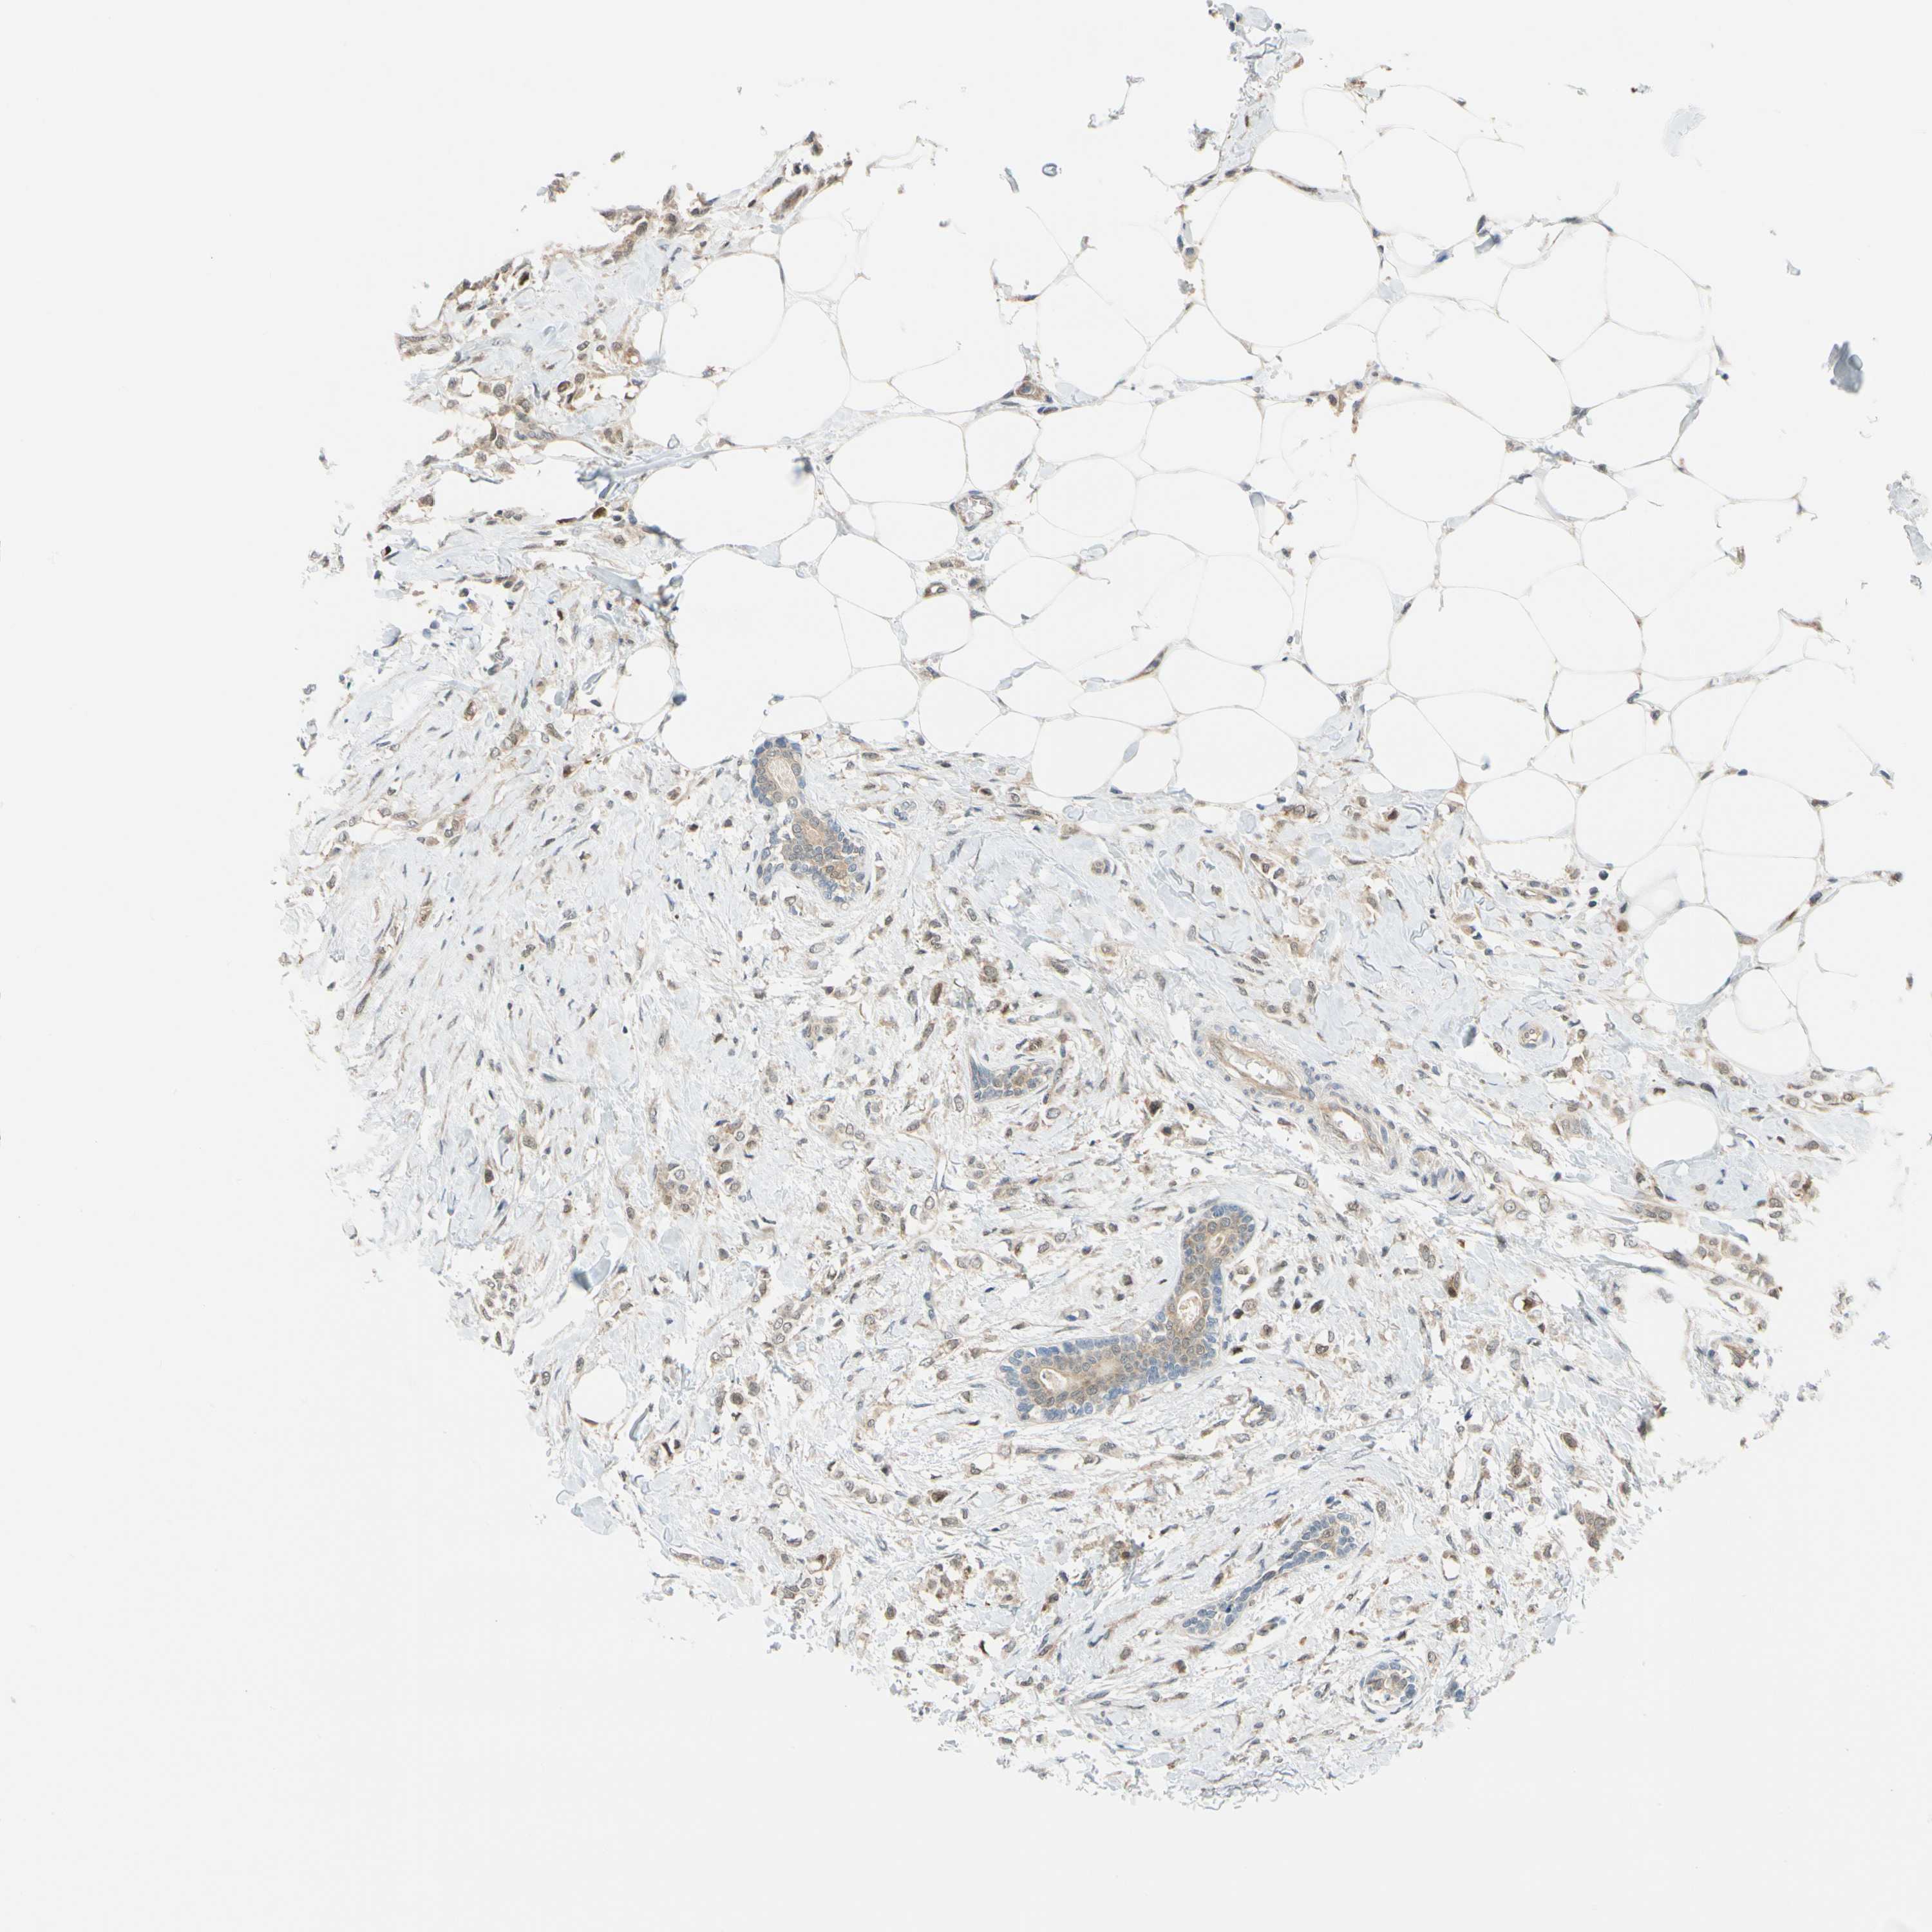

BRCA TCGA BRCA VALIDATION PROTEIN EXPRESSION